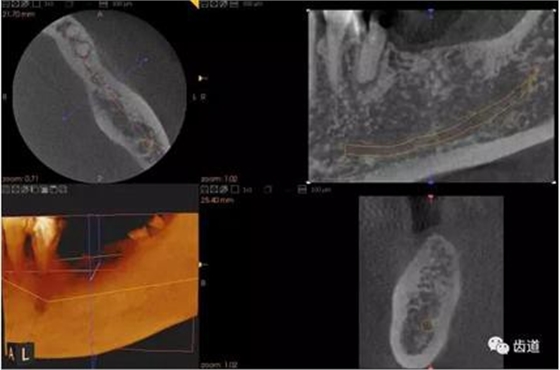

2、下頜磨牙阻生

下頜第二第三磨牙阻生口腔曲面斷層片影像

下頜第二第三磨牙阻生CBCT影像定位

三種圖片的影像學(xué)比較